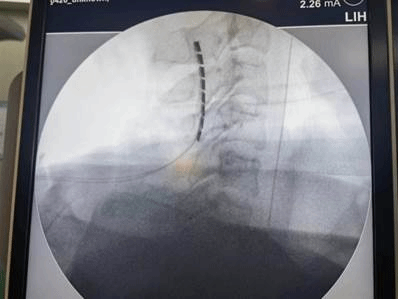

手术中骨科刘晓东副主任医师用C臂机定位电极植入位置

脊髓电刺激作为一种新型有效的植物人促醒技术,通过在高位颈髓植入电极,脉冲式放电由脊髓传入大脑,增加大脑血流量,激活神经系统,改善脑循环,兴奋大脑皮层,达到促醒的目的。经过缜密的术前准备,郭冕教授带领团队成功将刺激电极安置在患者颈2-4硬脊膜外,以增强脑干网状激活系统起始部意识冲动的输入,实现促醒。手术一周后顺利开机,目前宋先生电刺激反应良好,意识状态得到显著的改善。

植入的电极

电极植入成功